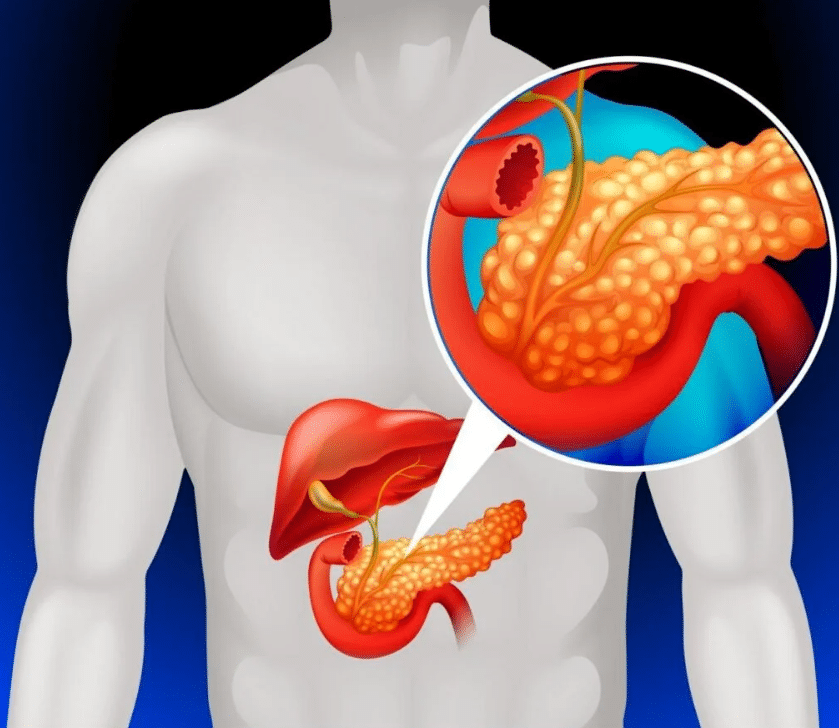

One disease known for developing in silence is pancreatic cancer. Because the pancreas sits deep inside the abdomen, behind the stomach, early problems can be difficult to detect. By the time symptoms become noticeable, the disease has often already advanced.

Pancreatic cancer can change the body’s chemistry in several ways. It may alter circulation, disrupt protein levels, and increase the tendency of blood to clot. These changes do not stay isolated in the pancreas. In some patients, they show up first in the legs.